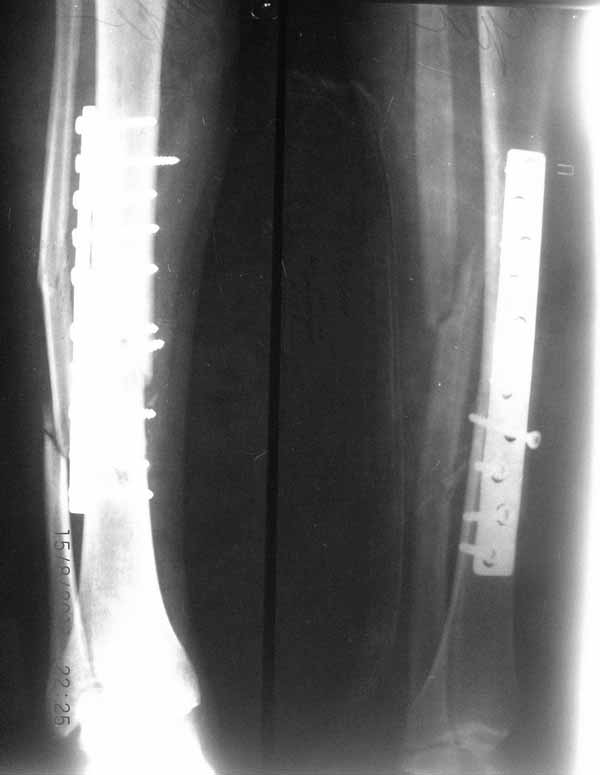

Примерная ситуация. Пациент 37 лет. Синтезировали где-то пластинкой. Попал к нам через 2 месяца.

19 апреля убрали через проколы пластину с винтами, пересекли fibula, наложили аппарат.

Немного потянули по оси, убрали вальгус, ротацию. 22 апреля (на 3-е сутки) заштифтовали окончательно. 29 апреля выписали из отделения. На все ушло 10 дней.

С уважением, Никита Заднепровский